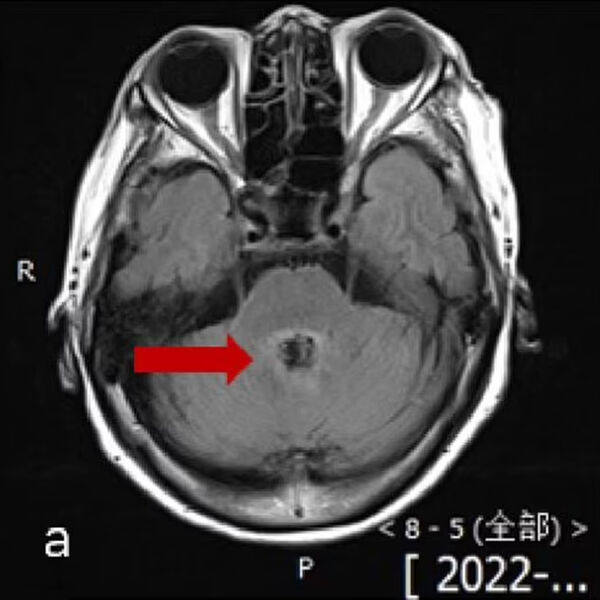

77-летняя пациентка обратилась в местную больницу в 2022 году с жалобами на головокружение, растерянность и трудности с речью, которые продолжались несколько дней. На снимках мозга врачи обнаружили поражение, которое могло быть раком. Однако анализ спинномозговой жидкости (образец получили с помощью укола в поясницу) показал, что пациентка была заражена одноклеточной амебой Balamuthia mandrillaris.